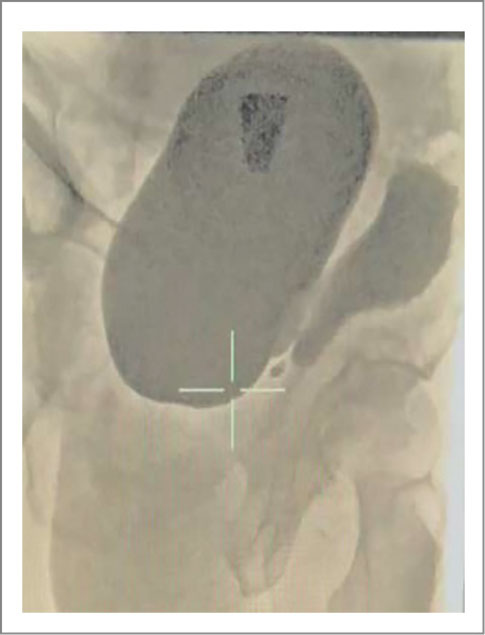

Пациент В., 68 лет, обратился за медицинской помощью с жалобами на боль в левой подвздошной области, чувство неполного опорожнения мочевого пузыря, слабую струю мочи на протяжении 8 мес. При УЗИ на левой стенке мочевого пузыря выявлен дивертикул, объем которого колебался в пределах от 400 до 700 мл. Объем мочевого пузыря составил 250–350 мл. Количество остаточной мочи в мочевом пузыре составило 56 мл, в дивертикуле – 604 мл (рис. 2).

Рис. 2. Пациент В., ультрасонограмма мочевого пузыря. Стрелкой указан ДМП.